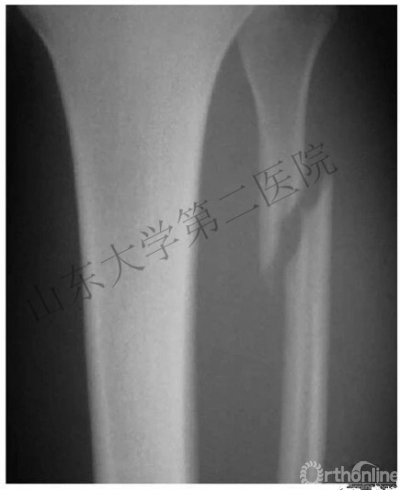

1. 骨间膜损伤及腓骨高位骨折

1.腓骨骨折的治疗

(1)对于远端2/3的腓骨骨折会引起腓骨短缩、外旋或外展畸形,对于此类骨折必须首先复位腓骨,恢复长度,纠正旋转。

(2)对于近端1/3的腓骨骨折无需固定。